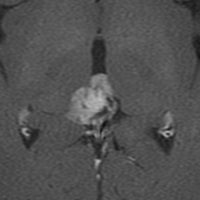

左はT1強調画像,右はFLAIR画像です。中脳視蓋が腫れて腫瘍がにじむように広がっているのがわかります。この腫瘍本体は15歳の時から21歳の時まで大きくなっていないので,中脳視蓋グリオーマ tectal gliomaの診断です。

T1強調ガドリニウム増強画像です。15歳の時は腫瘍の半分以上が強くガドリニウム増強されていましたが,この21歳の時の画像では,中心部やや右寄りに増強像が認められるだけです。この性質は,腫瘍が毛様細胞性星細胞腫であることを示しています。